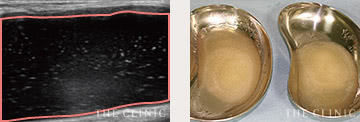

エコー画像と除去したヒアルロン酸 -

エコー画像と除去したヒアルロン酸

実際のエコー画像

-

溶解液注入

的確にしこりへ穿刺・注入 -

吸引・除去後

しこりの消失を確認 -

除去したヒアルロン酸

目視することで確実に除去